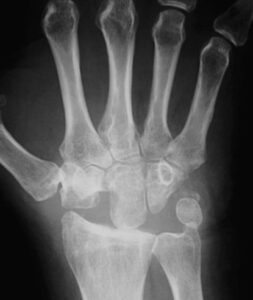

Diagram van de botjes die verwijderd worden bij proximale rij carpectomie. (Links) Radiografie van pols na proximale rij carpectomie (Rechts).

- Proximale rij resectie: het weghalen van de 1e rij handwortelbeenderen. Dit zorgt voor een voorspelbare afname van de pijn, echter er blijft een krachtsverlies en de pols verliest ongeveer 50% beweeglijkheid ten opzichte van een gezonde pols. Via een lengtesnee aan de rugzijde van de pols worden deze botjes weggehaald waardoor de 2e rij handwortelbeenderen met de onderarm een nieuw pols gewricht vormt.